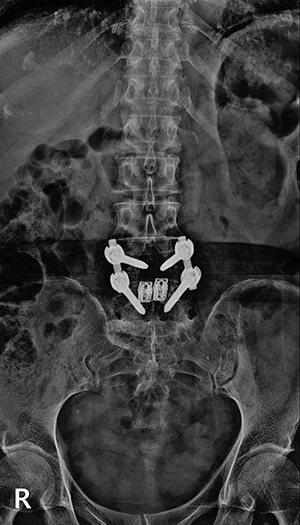

척추협착증수술, 척추유합술이란

척추유합술은 중증 척추관협착증, 허리디스크 재수술, 척추전방전위증에 많이 시행됩니다. 공통적으로 척추 뼈와 뼈 사이에 있는 디스크를 제거한 후 그 자리에 뼛가루 등을 채워 넣어 높이를 높여주고, 불안정해진 척추 뼈의 안정성을 높이기 위해 나사못을 박아 고정시키는 수술입니다. 이 과정에서 디스크는 완전히 제거되고, 문제를 일으키는 인대나 척추 뼈의 일부도 함께 제거됩니다. 그렇게 되면 디스크 자리에 채워 넣은 뼛가루 등이 시간이 흐르면서 위아래 척추 뼈를 붙임으로써 통뼈로 변합니다.

▼ 척추뼈 2개를 묶은 유합술 ▼

• 유합술 전면 X-ray

• 유합술 측면 X-ray

▼ 척추뼈 3개를 묶은 유합술 ▼